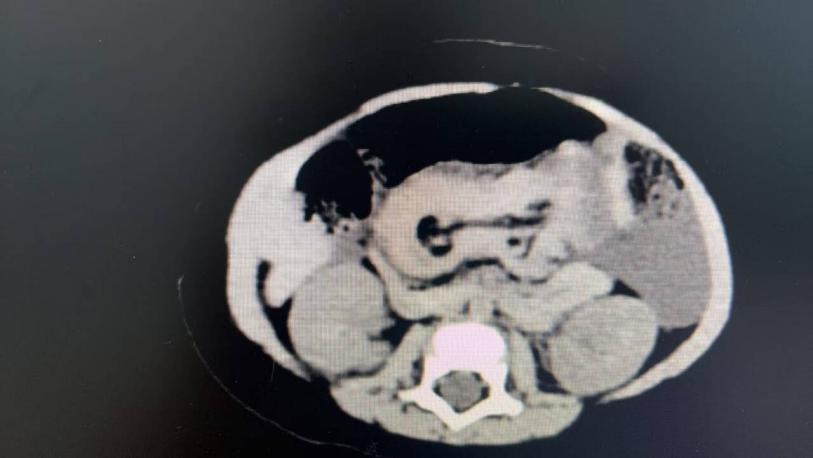

有了初步考慮,唐主任立即安排腹部彩超進一步明確診斷,可見中上腹同心圓征(考慮回回結(jié)型腸套疊)、腸間積液。由于腸套疊程度較重、時間較長,患兒出現(xiàn)精神萎靡、尿量減少等休克表現(xiàn),懷疑存在腸壞死或腸穿孔。此時只能選擇急診手術(shù)治療,挽救患兒生命!結(jié)果術(shù)中證實了回回結(jié)型腸套疊、腸壞死的診斷,做了腸切除吻合手術(shù)。

2  患兒術(shù)前CT